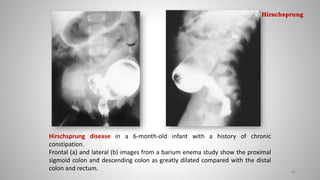

Hirschsprung disease in a 6-month-old infant with a history of chronic

constipation.

Frontal (a) and lateral (b) images from a barium enema study show the proximal

sigmoid colon and descending colon as greatly dilated compared with the distal

colon and rectum. 80